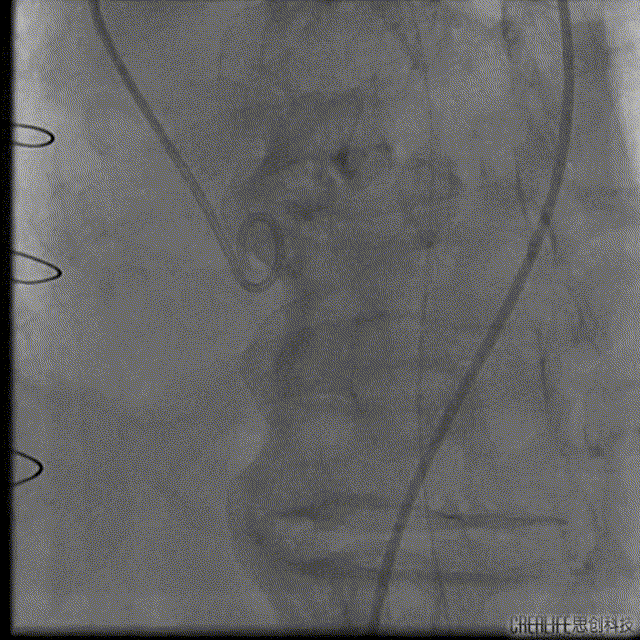

解剖上,这个患者虽然是右无融合的二叶瓣,但是右窦发育较小,形态上接近0型二叶瓣,瓣上钙化中,且集中在左窦,接近左右瓣叶联合部。瓣环及流出道平面较大,而瓣上结构较小,瓣叶联合部距离只有26,这种情况下只能考虑根据瓣上结构进行选择瓣膜。目标瓣膜为26号,为了避免破坏瓣上结构,我们选择26瓣膜的下限20号瓣膜进行与扩张。因为主动脉弓和升主动脉角度问题,没有选择plus。20球囊扩张可以看到左窦钙化很硬,右无联合可以推开,没有反流,故选择26号瓣膜,高位释放。释放后瓣膜下滑到标准位,有明显的腰,故用20球囊进行后扩展。最后造影虽然有中度瓣周漏,但是考虑患者狭窄解除,且升主动脉人工血管限制了瓣膜的流出端,未再行瓣中瓣。术中撤除ECMO,辅助循环约1小时。

Numed20后扩